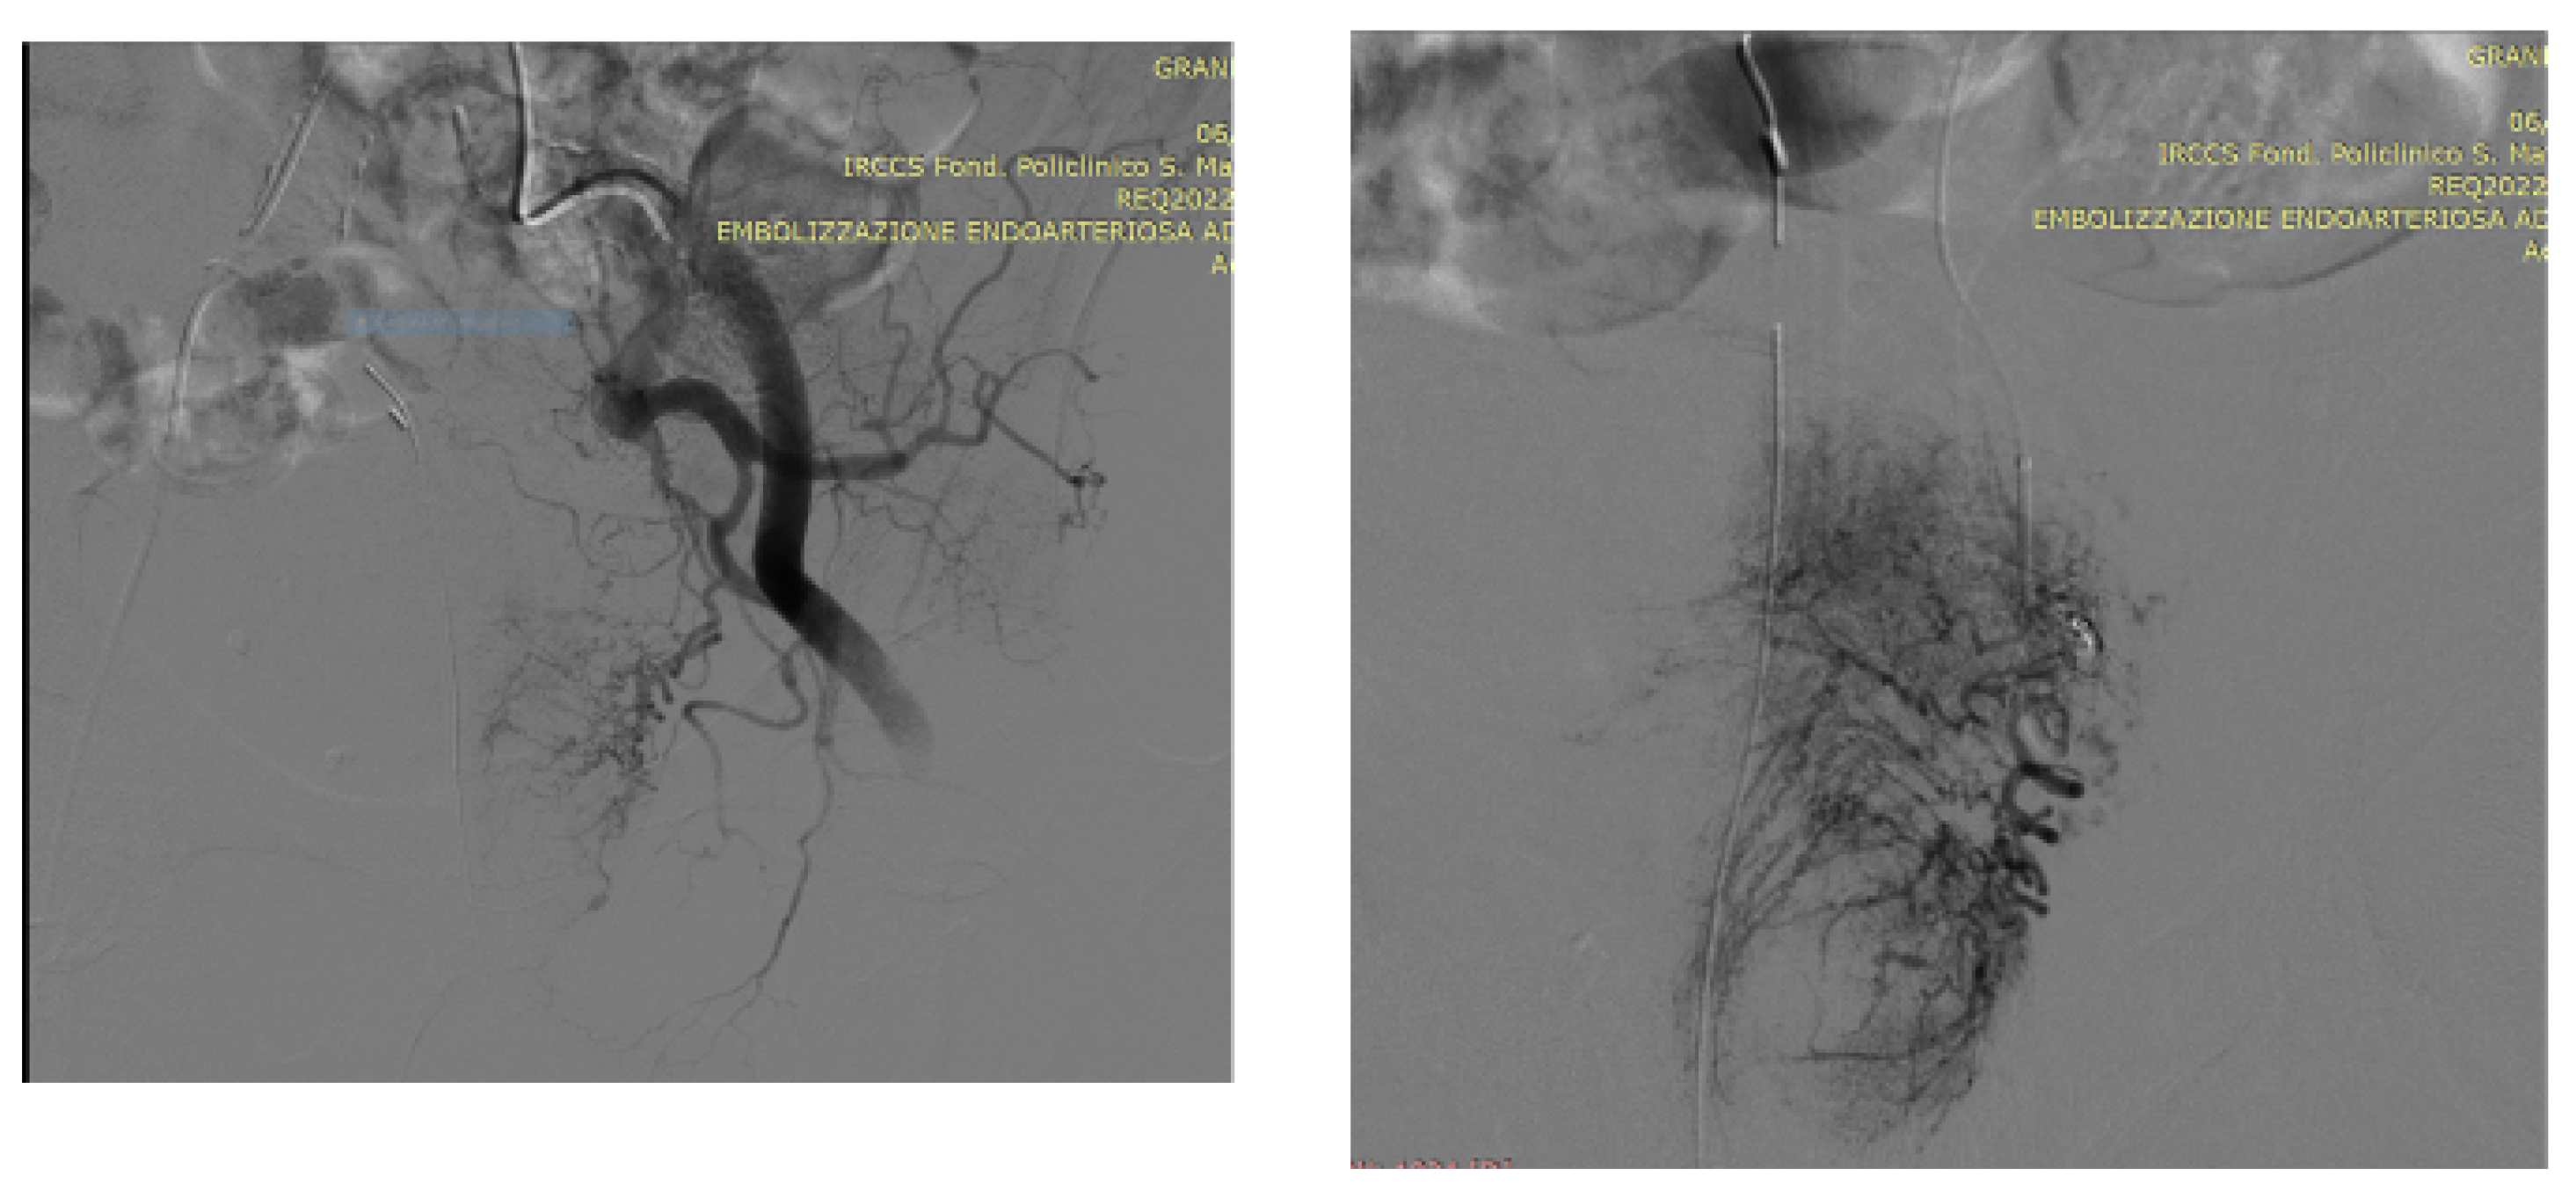

5. A Suggested Algorithm and a Demonstrative Case Report

Technical Details of PAE